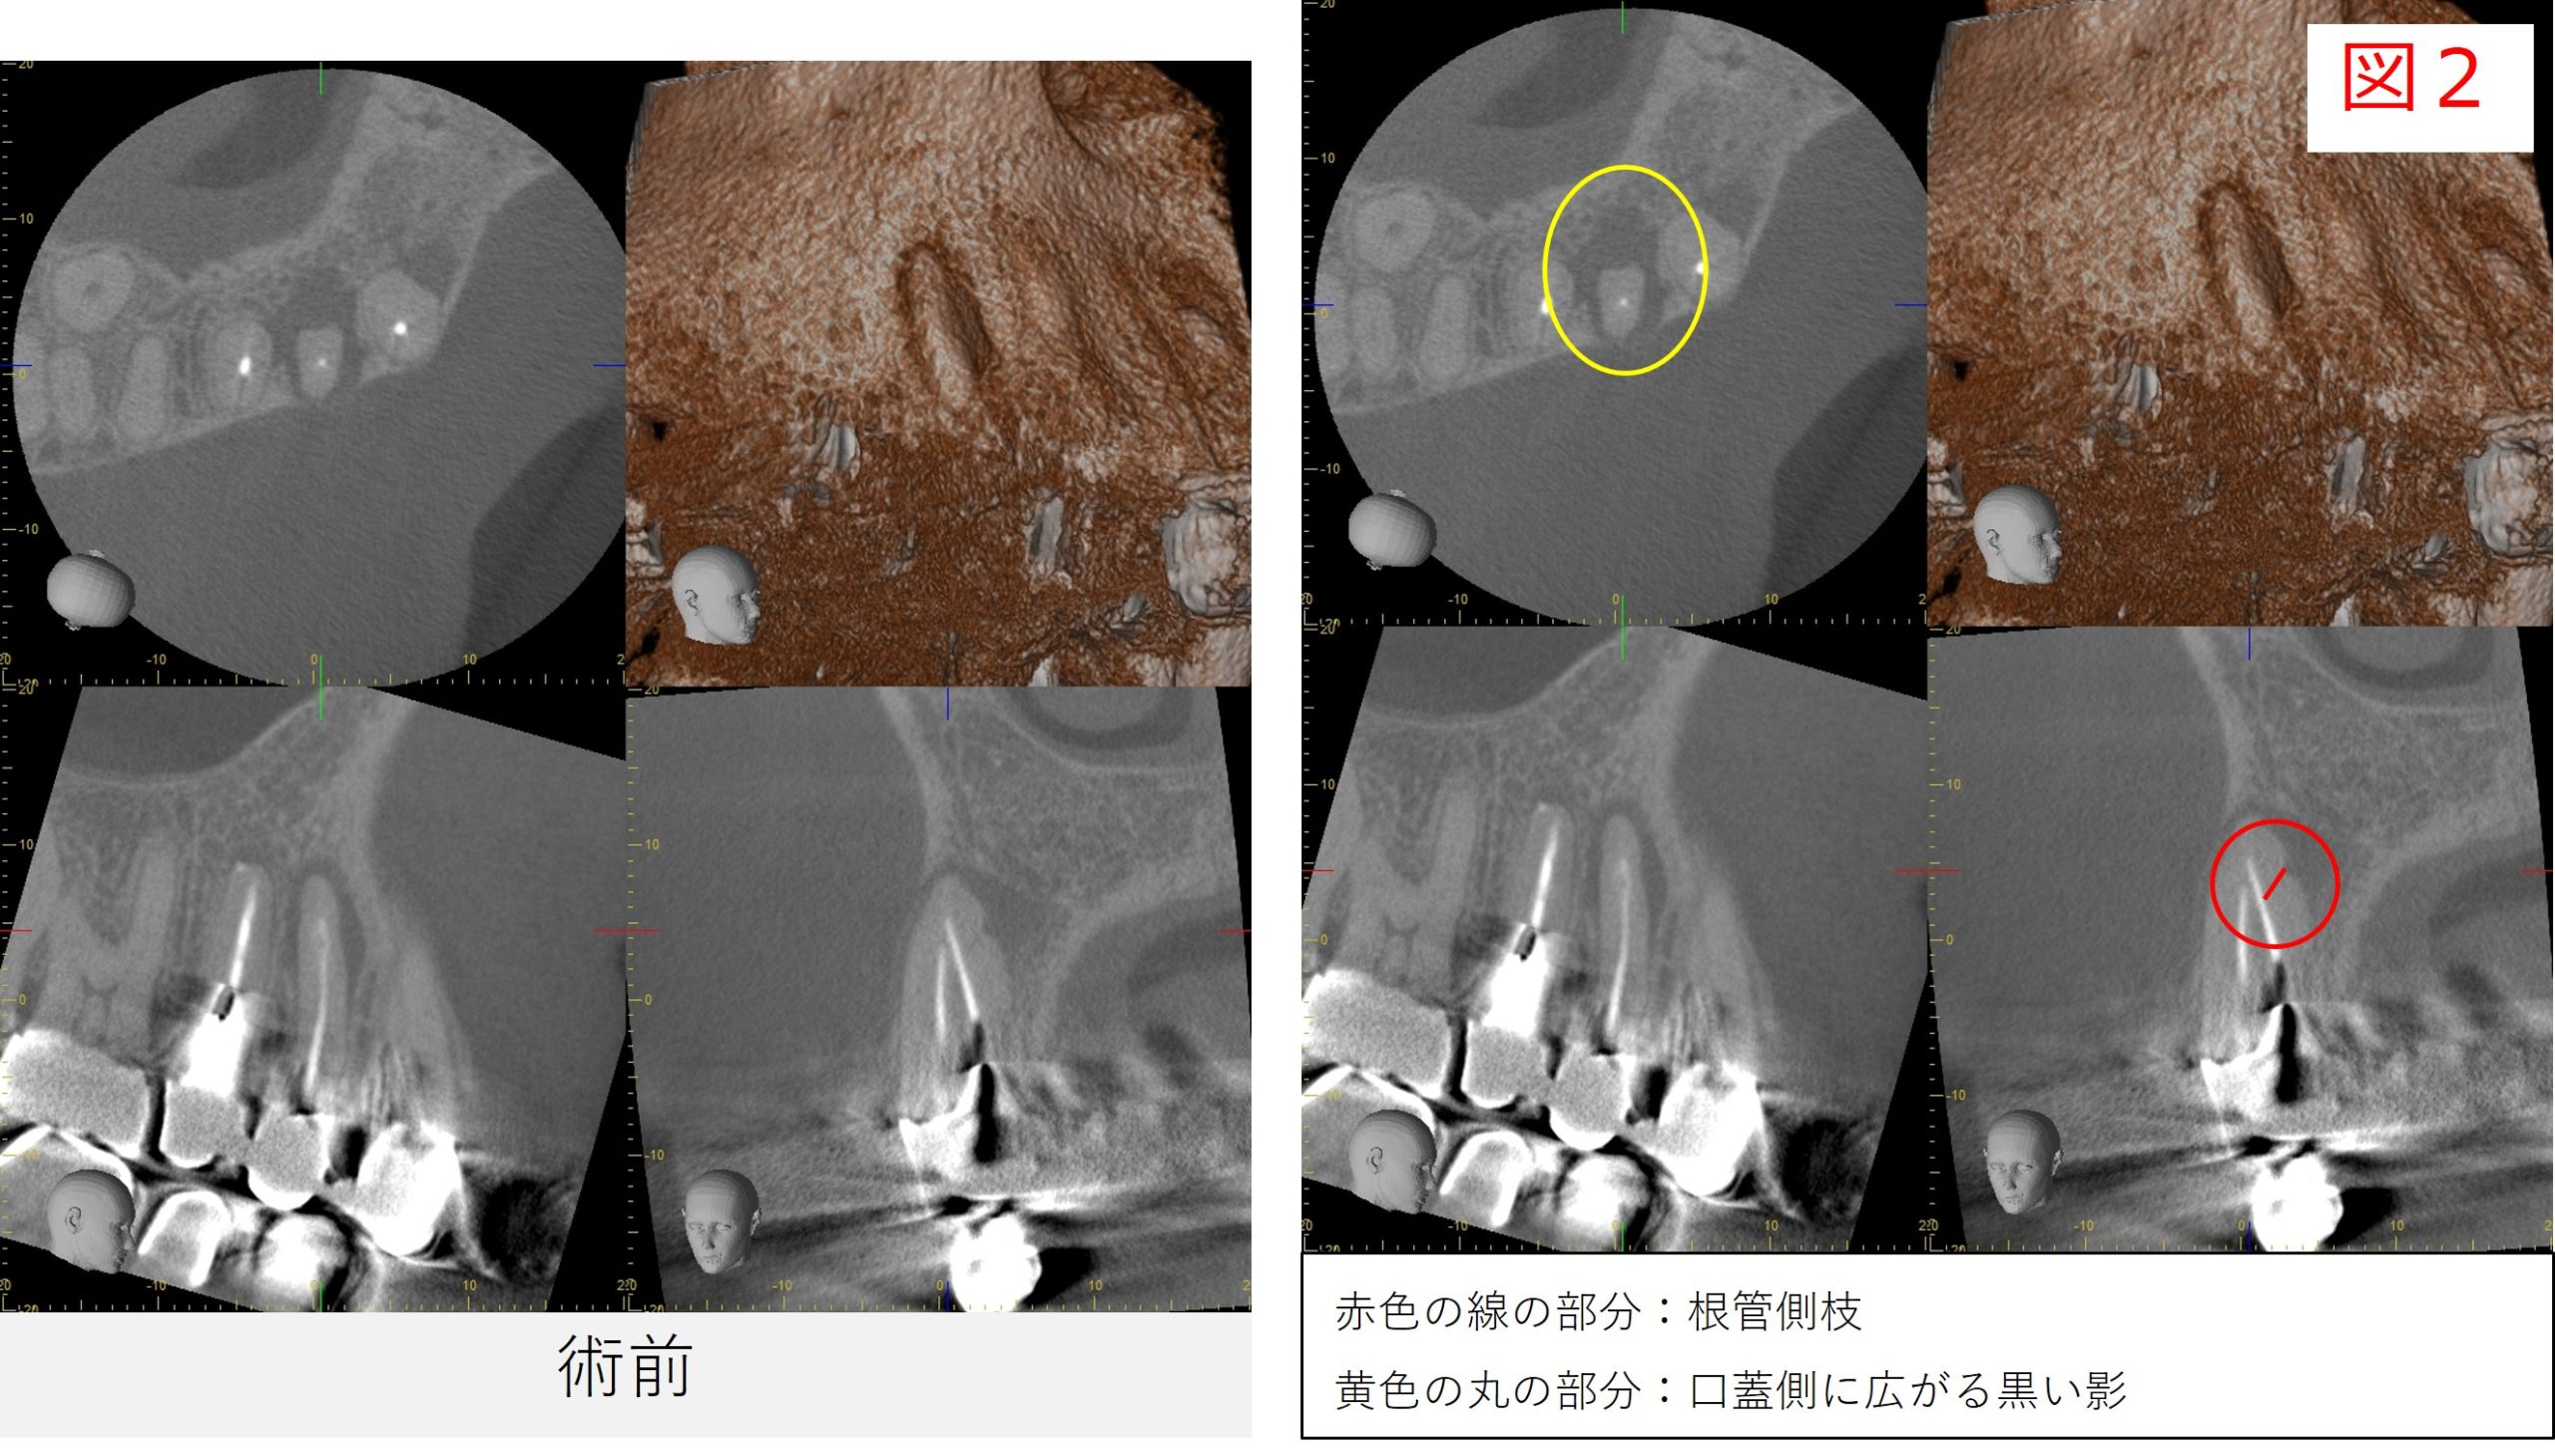

- レントゲンおよびCTで確認したところ、根の先や側面に見られていた透過像は縮小し、骨の回復傾向が確認されました。

- 特に、根の側面に見られていた透過像は、歯の根の途中から分かれている細い枝状の通路(側枝:そくし)に関連した炎症であった可能性が考えられます。

- 歯の根の内部は必ずしも一本のまっすぐな管だけではなく、途中で枝分かれしている細い通路が存在することがあります。

こうした側枝に感染が及んでいる場合、レントゲンやCTでは根の側面に黒い影として見えることがあります。

- 今回の症例では、根管治療後の経過観察でその透過像が縮小し、骨の回復傾向が確認されました。

- 炎症の改善がみられたため、最終補綴(被せ物の作製)へ移行する予定としました。